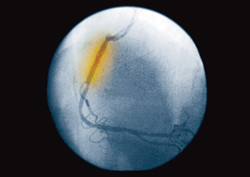

I en ny studie er det for første gang brukt biologisk nedbrytbare stenter i en koronararterie hos mennesker (1). 63 pasienter fikk implantert magnesiumstenter, som løses opp etter 2 – 4 måneder. Alle implantasjonene var vellykket, med god åpning av arterien. Etter fire måneder var det bare rester etter stentmateriale under intima, men halvparten av pasientene hadde fått restenose, og etter ett år hadde 45 % gjennomgått ny revaskularisering.

– Dette kan være fremtidens stenter, sier overlege Harald Vik-Mo ved Hjertemedisinsk avdeling, St. Olavs Hospital. – Men foreløpig er vi ikke i mål: Nesten halvparten fikk restenose med behov for ny behandling, og det er flere enn ved ballongdilatasjon alene. På den annen side viser studien at stentene lar seg plassere i arterier med høyt trykk uten å ta skade eller gi komplikasjoner, og at de oppløses fullstendig uten at fragmenter løsrives i sirkulasjonen.